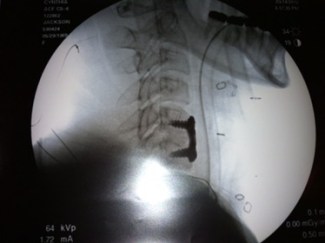

Convinced that this was still something different, I was determined to find the source ofthe neck pain/headaches/dizziness. I found a new rheumatologist for my Fibromyalgia, and he ordered an MRI for my neck pain. This eventually led to my diagnosis by neurosurgeon of a herniated disc in my neck at C5-C6, (anterior cervical discectomy) surgery in March, 2012, and relief from the pain and headaches due to the relief of pressure off of the spinal nerves.